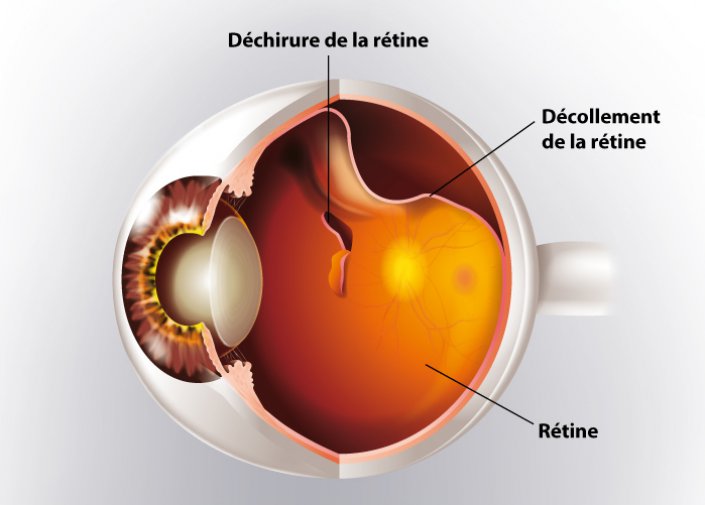

decollement retine photo Décollement de rétine

If you are searching about Décollement postérieur du vitré (DPV) | Institut de la rétine | CHU de you’ve visit to the right page. We have 35 Pictures about Décollement postérieur du vitré (DPV) | Institut de la rétine | CHU de like Le décollement de rétine - Pour la vision | Association CRO, Fond d’oeil_Décollement rétine supérieur avec déchirure rétinienne and also Décollement de rétine - Ophtalmologie l’Union. Read more: